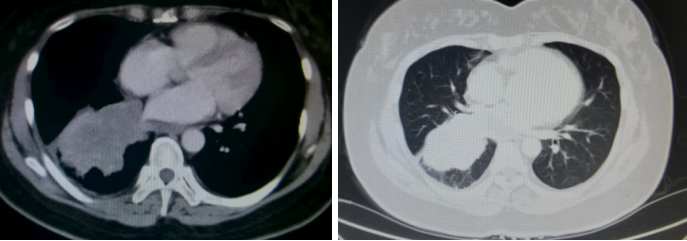

胸部CT(2024年4月8日):1. 右肺下叶见不规则软组织密度影,大小约8.2*6.7cm。2. 右侧胸腔少量积液。3. 肝脏多发占位,考虑转移。

腹部超声(2024年4月11日)